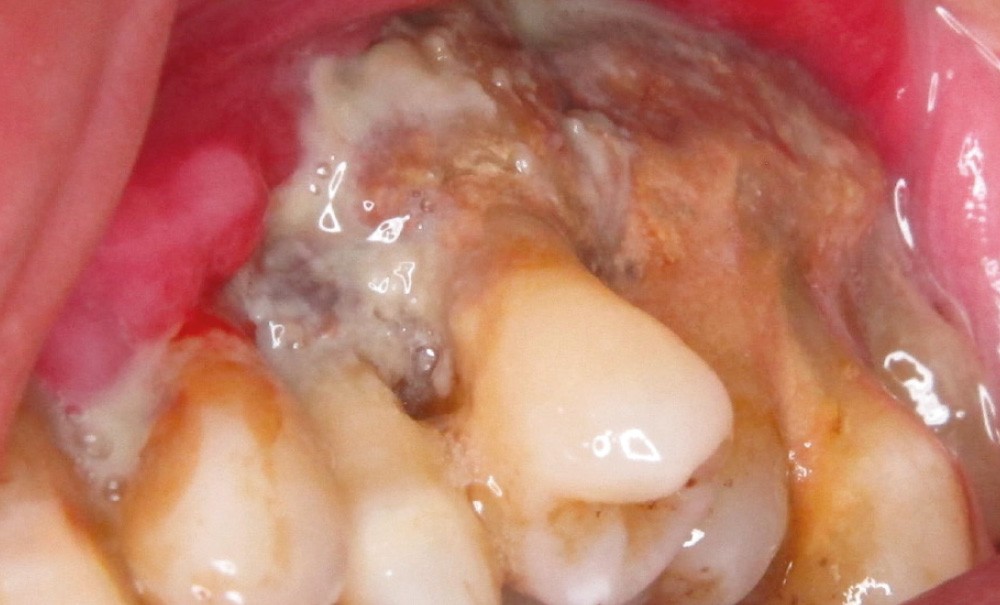

Les OCN

La physiopathologie des OCN liées aux antirésorbeurs osseux n’est pas encore complètement élucidée. Plusieurs hypothèses ont été proposées pour expliquer la localisation exclusive de l’OCN aux os maxillaires et mandibulaires. La diminution du remodelage osseux par inhibition de la résorption osseuse assurée par les ostéoclastes est le premier mécanisme évoqué. En effet, les bisphosphonates (BP) inhibent la résorption osseuse en induisant l’apoptose des ostéoclastes matures, et le dénosumab agit en empêchant la formation d’ostéoclastes…